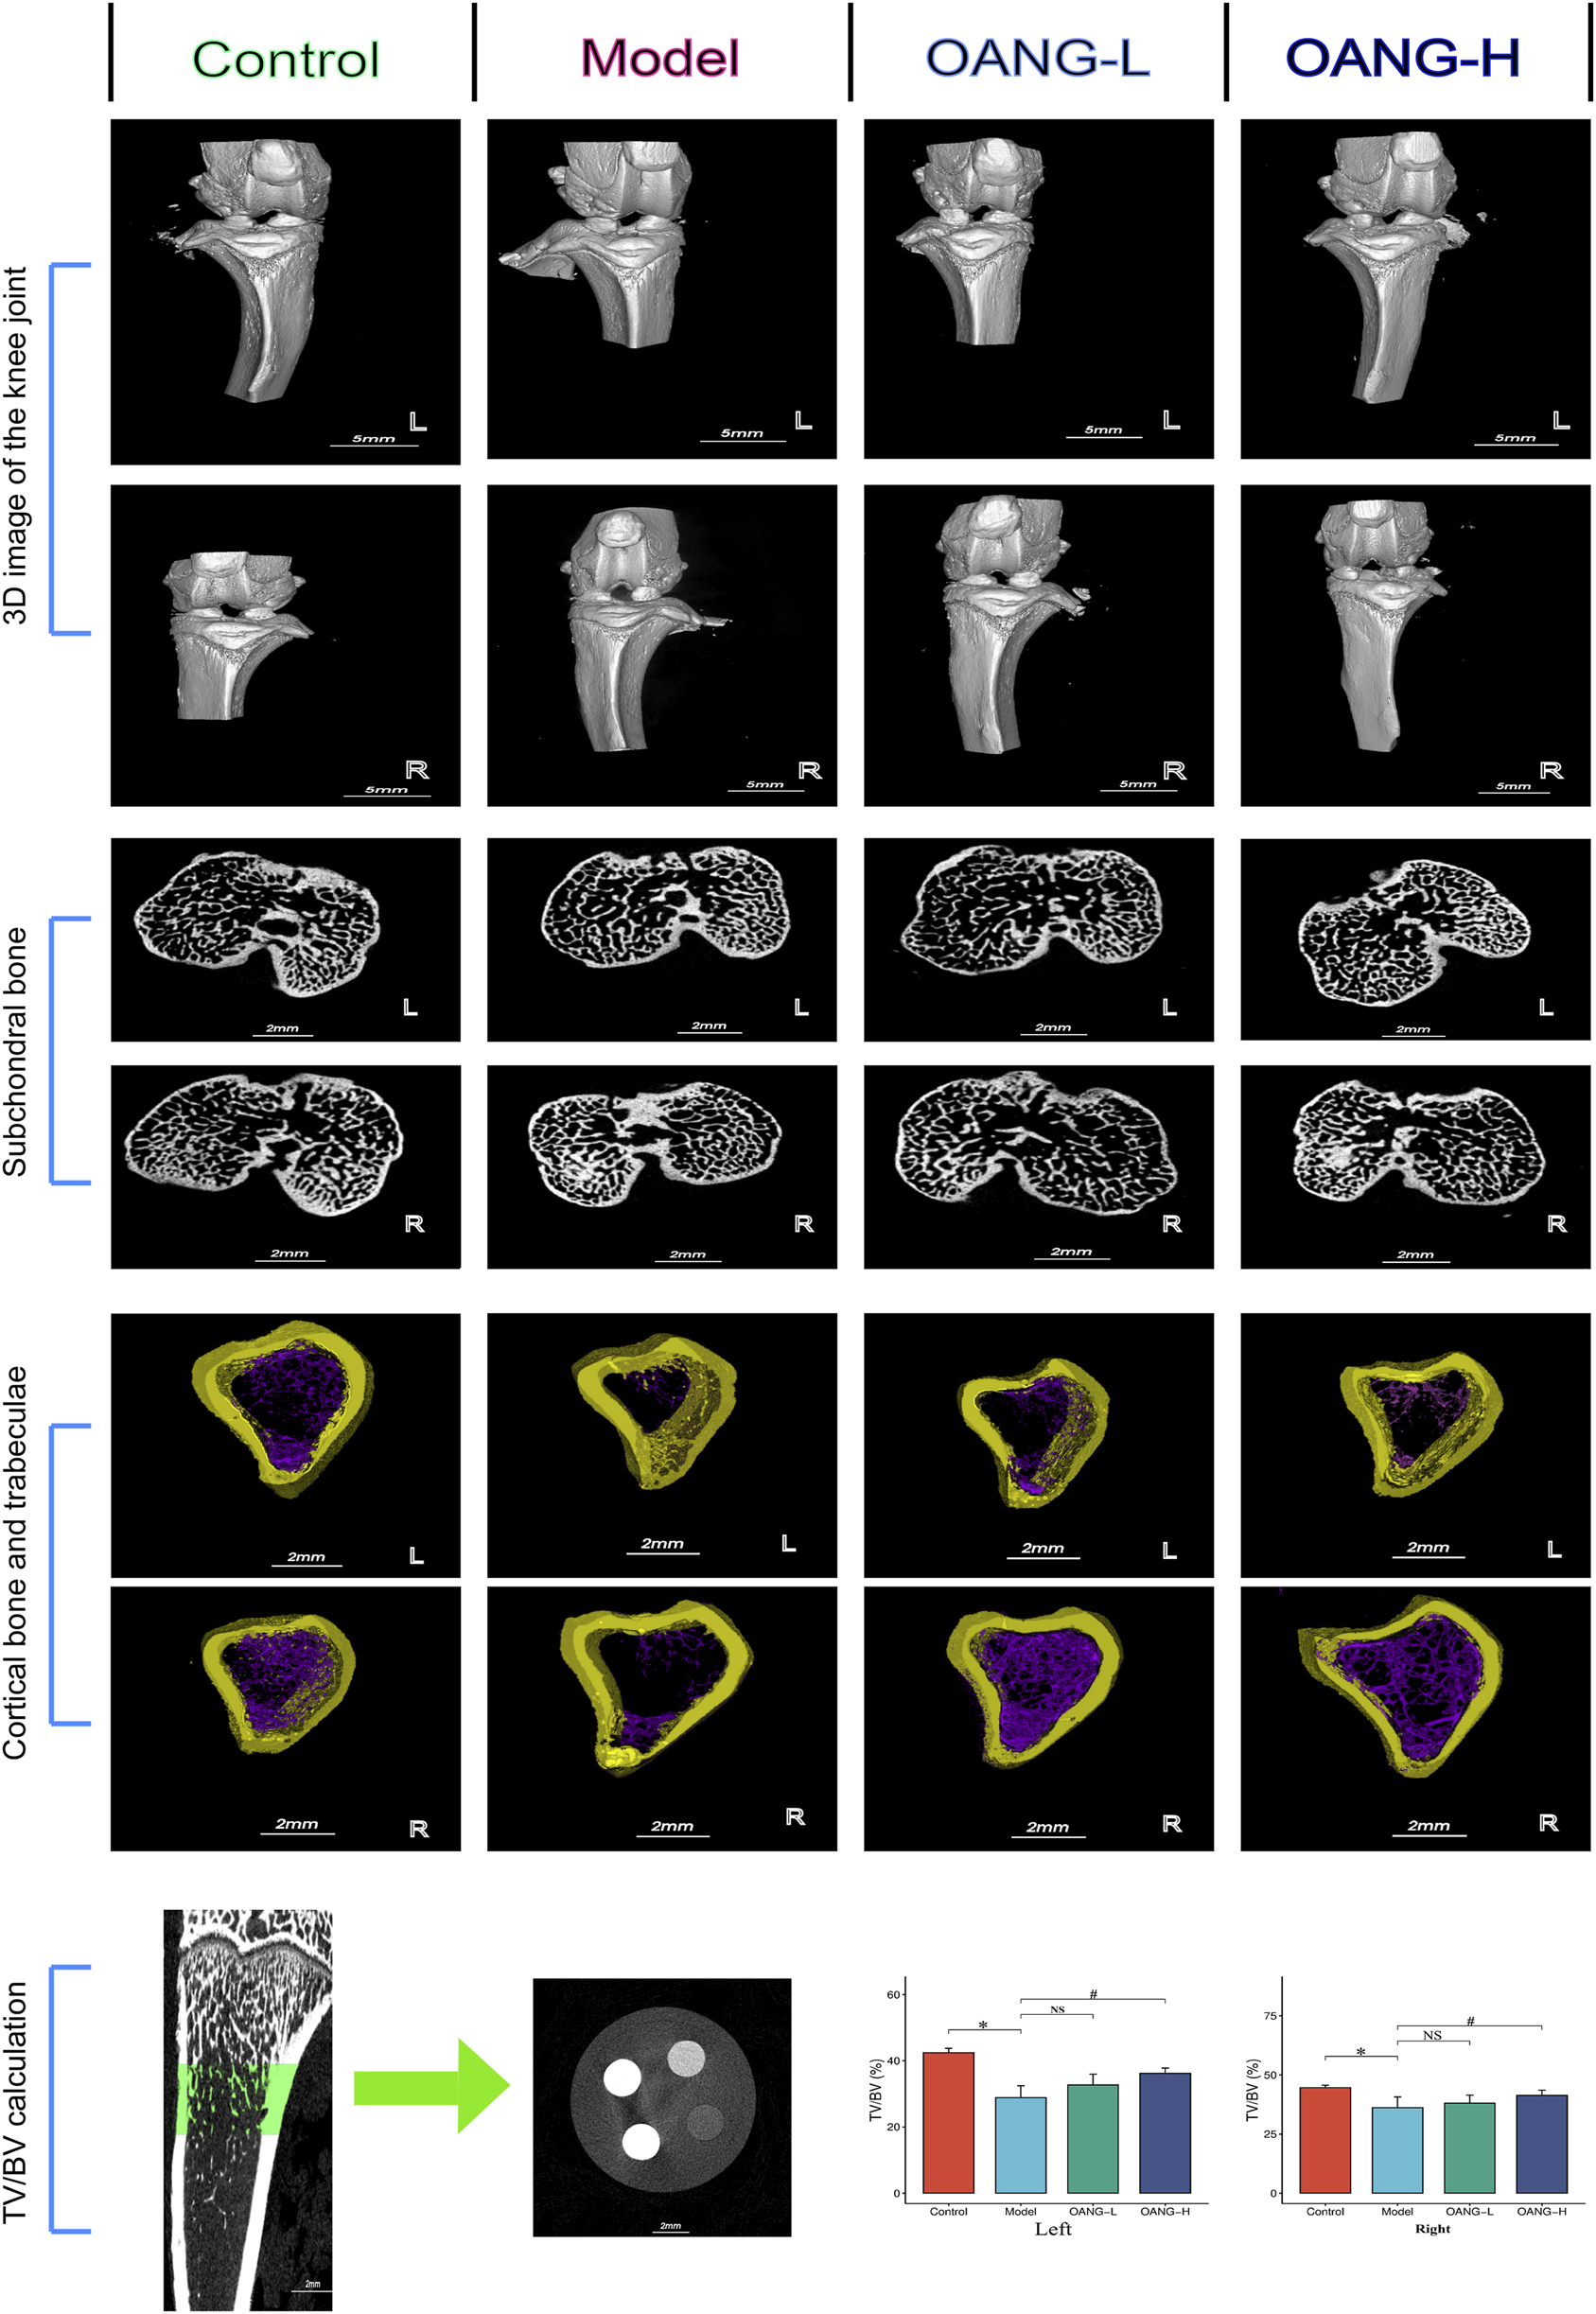

Micro-CT 3D reconstruction of the knee joint revealed decreased subchondral bone porosity in the Model group, indicative of osteosclerosis. OANG treatment reduced cartilage damage and increased porosity (Figures 2, 3D structure). The joint space was larger in the modeled left knee than in the right knee, but after OANG administration, porosity between the two knees became comparable, suggesting improved joint integrity.

FIGURE 2

Rat imaging findings results. Comparison with the control group, *P < 0.05; compared with the model group, #P < 0.05.

Cross-sectional analysis showed subchondral trabecular sclerosis in the Model group, likely resulting from mechanical wear and compensatory bone remodeling (Figure 2, subchondral bone). Sclerosis was more severe in the modeled left knee, but OANG treatment restored trabecular structure similarity between knees.

Avatar software-based analysis indicated trabecular reduction and loss in the Model group, which was ameliorated by OANG (Figure 2, cortical bone and trabeculae). Trabecular bone volume fraction was significantly reduced in the Model group; it was significantly improved in the OANG-H group but not in the OANG-L group (Figure 2, TV/BV calculation).